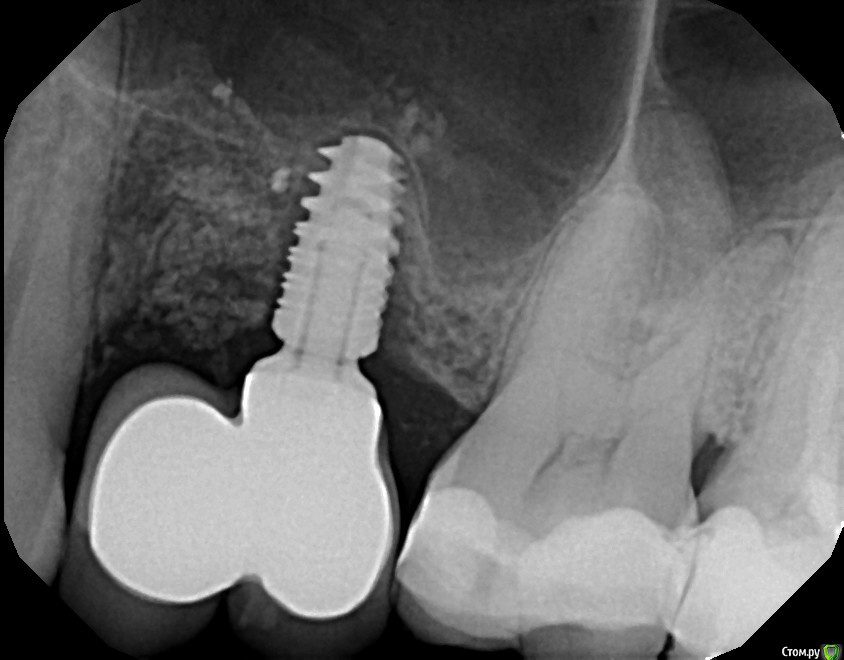

tonkin Опубликовано 9 января, 2017 Поделиться Опубликовано 9 января, 2017 Помогите определиться с числом имплантов. Отсутствуют 2 верхних зуба (в красном квадрате на пано). Расстояние между корнями ~ 16.5 мм. Вопрос следующий, какой вариант лучше (оба после планируемого синус лифтинга): 1) поставить 1 толстый имплант по центру с двойной коронкой, чтобы изобразить 2 зуба под улыбку. Тут смущает то, что в прошлом году уже такой вариант делали. Имплант расшатался за 3 месяца, и выпал (снимок импланта был сделан за 2 месяца до паноромного, где импланта уже нет). Вероятно, что имплант был коротковат для такой нагрузки (да и кости мало), и если сделать лучше, то будет держать двойную коронку нормально. 2) второй вариант - 2 тонких импланта с индивидуальными коронками, но места маловато (4 мм + 3 мм + 4 мм + 3 мм + 4 мм = 18 мм < 16.5 ). То есть все очень впритык. Смущает значительная добавочная стоимость, но с другой стороны, шатающегося импланта как в первом случае уж очень хочеться избежать. Мнения? И если стоимость - не вопрос, то будут ли 2 импланта лучше 1-го ? Дополнительный вопрос - как выглядят 2 нижних импланта на предмет качеста кости. Имплантам - 13 месяцев, коронкам - 7. Эти вроде пока держатся (тфу-тфу). Заранее благодарю за консультацию! Ссылка на комментарий

tonkin Опубликовано 10 января, 2017 Автор Поделиться Опубликовано 10 января, 2017 Огромное спасибо всем за ответы, но мнения оказались достаточно разные Если стоимость не вопрос - лучше будет пройти ортодонтическое лечение до имплантации.Расстояние между зубами как вы измеряли? На КТ, взял дистанцию от конца одного корня, до начала другого, или надо как то по другому ? Если ортодонтическое лечение, то нужно весь верхний ряд охватывать, или только зубы вокруг пустоты? И сколько времени это займет все подвинуть куда надо? Без ортодонтии 1 имплант, если создать место то два. Лучше ортодонтия и 2 импланта. Если без ортодонтии, то один имплант. А если таки поставить 2 рядом, с уменьшением рекоммендуемых расстояний ? Или такое вообще смысла не имеет ? С точки зрения эстетики десны лучше 1 имплантат с консолью ( не толстый по центру, а именно в позицию пятого зуба с консолью на 4й после ортодонтического лечения)+1 к bier (нагрузка не причём в этом случае) лучше 1 имплантатпроблема не в нагрузке, а в том, что недостаточная остеоинтеграция произошла. Где-то было 6 месяцев между имплантацией и коронкой. То есть вроде не так уж мало времени. И позиция была та, что надо, на 5м месте. На одиночном рентгене это имплант показан, когда он начал шататься, поэтому и щель уже. Получается, что нужно делать синус лифтинг, чтобы поставить 1 длинный имплант, который сможет консоль держать ? На снимке вроде имплант уже доходил до пазухи, то есть допольнительной кости сейчас нет. И еще десна частично провисла, то есть надо еще делать костную пластику со стороны десны ? Или это можно сделать вместе с установкой импланта ? Интересный момент что консоль действует как ключ, при повороте как бы откручивая имплант. Это то, как он начал шататься, через висячий 4й, и ощущения были поворота всей конструкции. Есть ли гарантия, что такое не повториться если все переделать, опять на 1 имплант ? Ссылка на комментарий

tonkin Опубликовано 1 июня, 2018 Автор Поделиться Опубликовано 1 июня, 2018 Обновление. Сделали мне дебелый синус лифтинг, кость наросла глубоко в синус. Гонял я туда-сюда, от имплантолога до протезиста. Оба мялись 1-2, непонятно. Но я, вспоминая ужасы консоли, которая раскручивала как монтировка 1 имплант, не хотел 1. В итоге протезист сделал шаблон, имплантолог загнал туда 2 импланта диаметром по 3.2 мм вроде и хорошей длины, в шахматном расположении, что бы увеличить расстояние между имплантами. Один из имплантов торчал немного не вертикально, в итоге протезист 3 раза делал слепок зубов, чтобы с лабой склепать 2 отдельные коронки. Но в конце концов вроде сделали. Потом он эти коронки долго и нудно подтачивал, и подварил немного материала чтобы между коронками улучшить контакт. В общем таки их приклеели, посмотрим теперь, как они будут держаться, и как обростут десной. Ссылка на комментарий